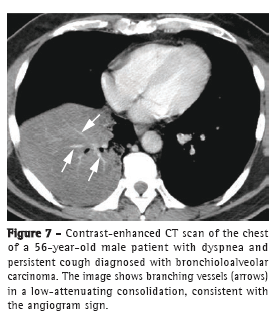

The angiogram sign can be seen on contrast-enhanced CT scans and consists of branching pulmonary vessels in a low-attenuating consolidation (Figure 7), usually corresponding to air spaces filled with mucin. First described as being specific to the pneumonic form of BAC, the angiogram sign can be seen in numerous entities, such as infectious pneumonia, pulmonary edema, postobstructive pneumonia, lymphoma, and metastases.(19)